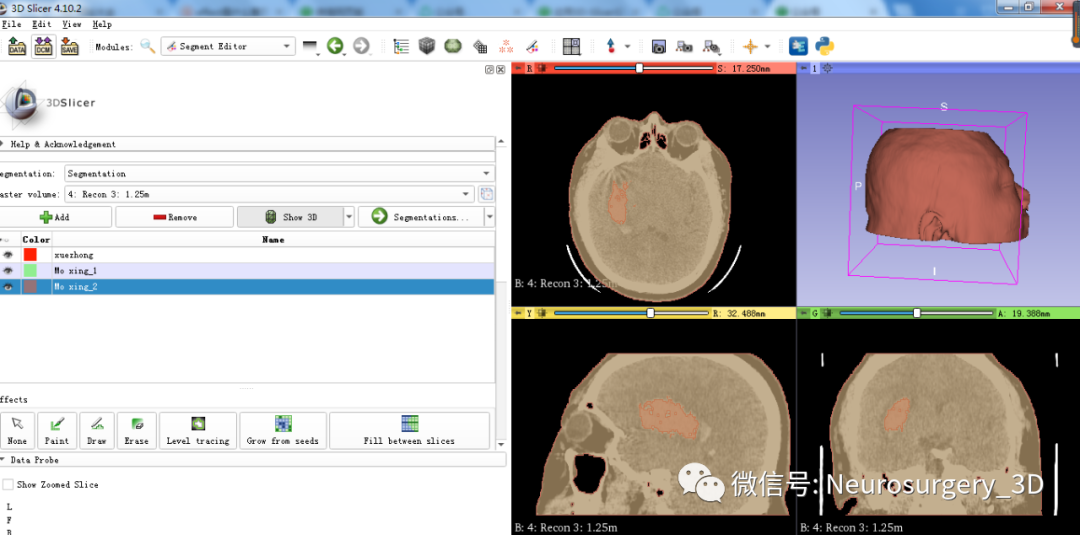

1、在同等阈值-200至3071状态下增加设置segment_1、segment_2并重新命名为Mo xing_1、Mo xing_2。

2、利用Margin![]() 中的Grow膨胀Mo xing_2,可见图中红褐色大于绿色模型。

中的Grow膨胀Mo xing_2,可见图中红褐色大于绿色模型。

3、利用Logical operators逻辑运算模块中相减功能得出头颅面具模型。